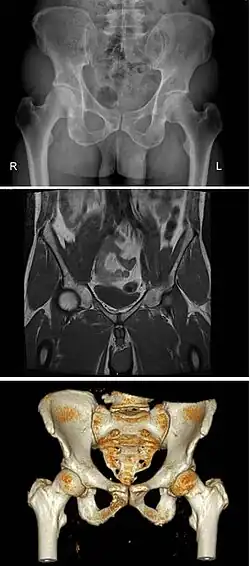

Variation

Modern humans are to a large extent characterized by bipedal locomotion and large brains. Because the pelvis is vital to both locomotion and childbirth, natural selection has been confronted by two conflicting demands: a wide birth canal and locomotion efficiency, a conflict referred to as the "obstetrical dilemma". The female pelvis, or gynecoid pelvis,[8] has evolved to its maximum width for childbirth—a wider pelvis would make human females unable to walk. In contrast, human male pelvises are not constrained by the need to give birth and therefore are more optimized for bipedal locomotion.[9]

The principal differences between male and female true and false pelvis include:

- The female pelvis is larger and broader than the male pelvis which is taller, narrower, and more compact.[10] The female pelvis is lighter and thinner than the male pelvis.[11]

- The female inlet is larger and oval in shape, while the male sacral promontory projects further (i.e. the male inlet is more heart-shaped).[10]

- The sides of the male pelvis converge from the inlet to the outlet, whereas the sides of the female pelvis are wider apart.[12]

- The angle between the inferior pubic rami is acute (70 degrees) in males, but obtuse (90–100 degrees) in females. Accordingly, the angle is called subpubic angle in males and pubic arch in females.[10] Additionally, the bones forming the angle/arch are more concave in females but straight in males.[13]

- The distance between the ischia bones is small in males, making the outlet narrow, but large in females, who have a relatively large outlet. The ischial spines and tuberosities are heavier and project farther into the pelvic cavity in males. The greater sciatic notch is wider in females.[13]

- The iliac crests are higher and more pronounced in males, making the male false pelvis deeper and more narrow than in females.[13]

- The male sacrum is long, narrow, more straight, and has a pronounced sacral promontory. The female sacrum is shorter, wider, more curved posteriorly, and has a less pronounced promontory.[13]

- The acetabula are wider apart in females than in males.[13] In males, the acetabulum faces more laterally, while it faces more anteriorly in females. Consequently, when males walk the leg can move forwards and backwards in a single plane. In females, the leg must swing forward and inward, from where the pivoting head of the femur moves the leg back in another plane. This change in the angle of the femoral head gives the female gait its characteristic (i.e. swinging of hips).[14]